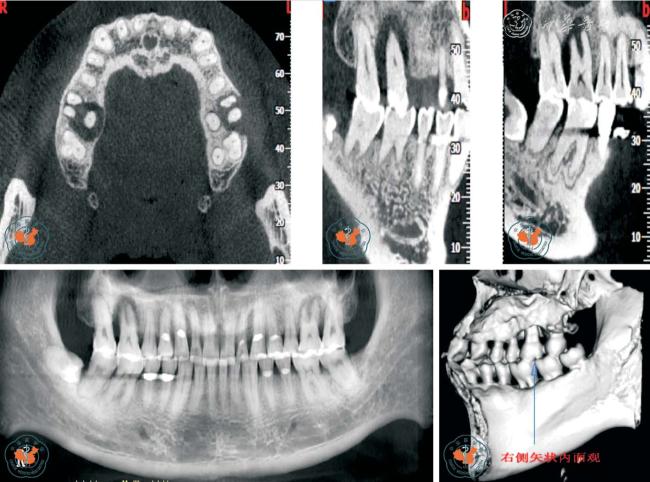

3. 对根管治疗术质量的评价:CBCT 图像可了解牙髓组织的解剖结构,特别是在复杂根管治疗前及术中,可以随时调用近远中向、冠根向、颊舌向的解剖图像,从不同的方向及断层进行切片分析,能够清晰地了解根管的形态,帮助根管治疗,使治疗更彻底,根管治疗后还可以用来监测根管治疗效果,减少了漏诊(图5)。

图5 CBCT 轴位、CPR 及MPR 重建冠、矢状位图像清晰显示上颌第一、二磨牙(牛牙症)

4. 对牙根折根裂诊断的意义:牙根折裂临床上分为纵折、横折及斜折三种类型。 在很多情况下,牙根折(特别是纵折)一般不易在根尖片上清楚显示,只表现为患根周围的牙周膜增宽,或出现J 形牙槽骨吸收,而看不到明显的根折线。 另外由于投照角度可影响X 线片的检出率,加上重叠的解剖关系干扰了读片医生的判断能力,因而早期患者经常存在漏诊。 而CBCT 则可以通过矢状面(近远中向)、冠状面(颊舌向)及水平面(冠根向)清晰的显示出根折线,同时清晰的显示出根折位置及类型,也可以对传统的根尖片疑似根折的病例用三维立体的图像进行直观的分析以明确诊断(图6)。 Hassan 等14研究显示,X 线与CBCT 对牙根纵裂的诊断能力,并评估根充材料对诊断牙根纵折的影响,结果显示CBCT 对诊断牙根纵裂的敏感度及特异度分别为79.4%与92.5%,根尖片发现牙根纵裂的敏感度及特异度分别为37.1%与95%,CBCT 检出牙根纵折的准确度明显高于根尖片。 另外,Hassan 还分析了根管充填材料对于牙根纵折检出的影响。 结果表明根充材料的存在降低了CBCT 的特异度,但未影响其准确率。 而对于根尖片,根充材料的存在既降低了其敏感度,也对其准确率造成了影响。 尽管CBCT 有上述优势, 但应注意致密根充材料和金属桩核在CBCT 图像中造成的高低密度混杂的放射状伪影,会产生与根裂纹相似的影像,应仔细辨别,以防误诊15

图6 CBCT 轴位、VR 及MPR 重建冠、矢状位图像清晰显示根折线